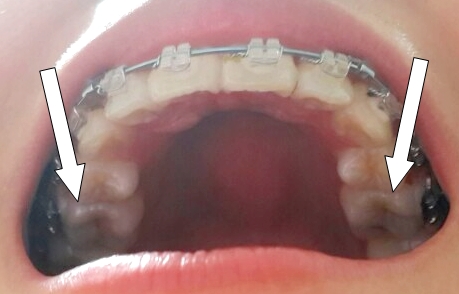

KakaoTalk_20150401_222647132.jpg

1년만에 바이트 블록에 가려있던 제 어금니를 보니 신기하기도하고

바이트블록에 익숙해져있어서 그런지, 어색했어요 ~

바이트블록 제거한 부분의 교합을 맞추기위해서

고무줄은 한칸 뒤로 이동했어요

KakaoTalk_20150401_222646959.jpg

너무 깊숙한 곳이다보니 , 잘 안걸어지더라구요 ㅎㅎ